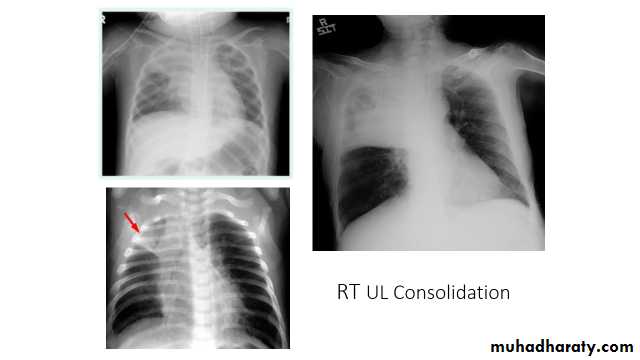

Right upper lobe consolidation

RUL consolidation will be seen as an increased opacity within the right upper lobe. Opacity may be sharply bordered by the horizontal fissure

Some loss of outline of the upper right heart border may be apparent

Radiological sign in chest radiograph

Dense opacity seen above the horizontal fissure.

Air-bronchogram line

The lower border of the consolidation is sharply delinated by the horizontal fissure suggesting it lies in the anterior segment of the RUL